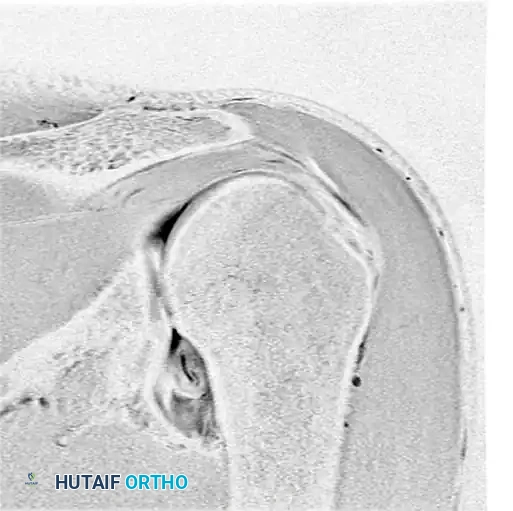

Preoperative magnetic resonance imaging (MRI) or MR arthrography is essential for identifying specific capsuloligamentous injuries. One such critical finding is the Humeral Avulsion of the Glenohumeral Ligament (HAGL) lesion, which can be easily missed if not specifically sought.

Figure 47-32 (A, B, C): MR angiograms demonstrating a HAGL lesion. Note the characteristic J-sign indicating the avulsion of the inferior glenohumeral ligament from its humeral attachment.